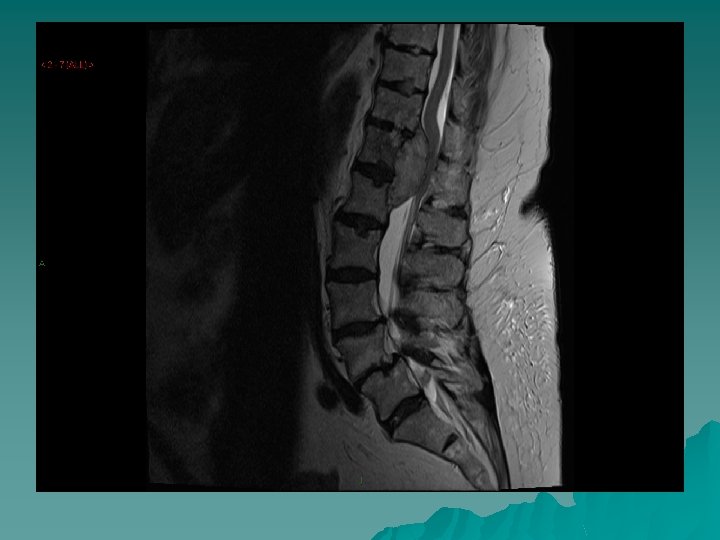

Diagnosis u In the history - especially in a known cancer patient. u MRI spine – urgent u Referral to Oncology - urgent

Aetiology 3 routes: u Vertebral mets invading the epidural space, or causing bone destruction and fragments of bone compressing the cord u Retroperitoneal tumours grow through the intervertebral foramina u Compression of blood supply to cord causing ischemia and oedema and hence loss of function